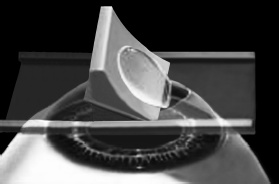

ЛАСИК – основной метод лазерной коррекции в мире в настоящее время. По большому счету, ФРК и ЛАСИК – единственные методы коррекции. Остальные методы являются либо модификациями ФРК и ЛАСИК, либо «компромиссом» между ними. Эпителий роговицы не трогают, так как он – залог быстрого заживления. Накладывают на глаз вакуумное кольцо – стальную присоску кольцевидной формы с присоединенной к нему трубочкой. Через трубочку из присоски отсасывается воздух, чтобы создать относительный вакуум. Отсасывает воздух главный аппарат для проведения ЛАСИКа – микрокератом. Это прибор размером с коробку из-под обуви. Его предназначение – срезание поверхностной крышки роговицы. К глазу присоединяют вакуумное кольцо, окружающее роговицу. Глаз четко фиксируется относительно кольца и сдвинуться с места может только с кольцом, в отверстие которого выступает купол роговицы. Затем к кольцу присоединяется головка микрокератома. Это второй инструмент микрокератома и соединяется с ним или шнуром, или тонким шлангом. Головка крепится на турбине, и вместе они имеют вид толстой шариковой ручки с обрубленным концом. Эту «ручку» хирург держит в правой руке, а вакуумное кольцо – в левой. Эта «ручка» нужна, чтобы сформировать крышечку роговицы. Внутри головки есть очень острое одноразовое лезвие. Турбина, соединенная с головкой, может двигать одноразовое лезвие туда-сюда, пилящими движениями. Можно резать роговицу, как хлеб, – пилящими движениями. И тут самое главное – скорость. Одноразовое лезвие делает 15000 пилящих движений в минуту. При такой скорости назвать это срезанием роговицы уже трудно, скорее это отслаивание верхних слоев. ![]() Рис. 3. Схема формирования роговичного лоскута с помощью микрокератома. Иллюстрация с сайта Международного лазерного центра www.optics.ru Итак, головка присоединяется к вакуумному кольцу и по специальным полозьям двигается над куполом роговицы (рис. 3). Срез, или отслаивание (называйте, как хотите), проводится не полностью, у крышечки (роговичного лоскута) остается маленький участок на периферии, соединяющий ее с роговицей (рис. 4). ![]() Рис. 4. Роговичный лоскут сформирован. Иллюстрация с сайта Международного лазерного центра www.optics.ru После формирования роговичного лоскута убирают инструменты микрокератома, затем шпателем откидывают его вбок (рис. 5). Обнажается роговичное ложе, то есть место, на котором лежал лоскут. Это верхние слои стромы роговицы. Ложе осушают тупфером и так же, как и при ФРК, настраивают лазер и испаряют несколько микрон вещества стромы (рис. 6). Потом промывают строму водой и шпателем укладывают лоскут на место. ![]() Рис. 5. Роговичный лоскут откинут в сторону. Иллюстрация с сайта Международного лазерного центра www.optics.ru ![]() Рис. 6. Луч эксимерного лазера испаряет на роговичном ложе несколько микрон стромы роговицы. Иллюстрация с сайта Международного лазерного центра www.optics.ru Стоит один раз моргнуть и лоскут скомкается и зрения не будет. Его бы пришить на место. Но швы деформируют роговицу. Все проще. Лоскут разглаживают мокрым тупфером, прижимая его ровненько к старому месту (рис. 7 и 8). Только место не старое, с роговичного ложа удалили несколько микрон в виде причудливой ямки (при коррекции близорукости). ![]() Рис. 7. При коррекции близорукости на роговичном ложе формируется «ямка». Иллюстрация с сайта Международного лазерного центра www.optics.ru ![]() Рис. 8. Роговичный лоскут укладывается на место. Иллюстрация с сайта Международного лазерного центра www.optics.ru Края роговичного лоскута осушают сухим тупфером. Влага, оставшаяся под лоскутом в ямке роговичного ложа, высасывается в тупфер. Лоскут притягивает к ложу, как вакуумную присоску. Вакуумом начали, вакуумом закончили. Ждем, когда закончится приживление лоскута к ложу. Эпителий цел и невредим. А значит, никаких болей. Около трех часов возможны слезотечение и светобоязнь. И все (рис. 9). ![]() Рис. 9. Форма роговицы до проведения коррекции (а) и после коррекции близорукости (б). Испарение нескольких микрон толщины роговицы привело к уменьшению ее кривизны в центре. Иллюстрация с сайта Международного лазерного центра www.optics.ru Хирурги о ЛАСИКе говорят: «90 % хирургии и 10 % долечивания». Лазерный субэпителиальный кератомилез (LASEK) Модификация ФРК. Чтобы укоротить неприятный послеоперационный период, эпителий, обработанный спиртовым или солевым раствором, отслаивают очень бережно, с помощью специальных инструментов, в виде цельного лоскута. А после испарения эксимерным лазером боуменовой мембраны и нужного количества слоев стромы этот эпителиальный лоскут укладывают обратно и, чтобы он не сместился, прижимают мягкой контактной линзой. Через 3–4 дня эпителий заживает, а благодаря линзе и даже еще не приживленному эпителиальному лоскуту боль и светобоязнь не беспокоят пациента с первых часов после коррекции, а зрение восстанавливается на пару недель быстрее, чем при ФРК. Также одной из модификаций ФРК является MAGEK. Основным отличием от ФРК является применение препарата Митомицин С (Mitomycin-С), который блокирует «слишком быстрое деление клеток» и снижает риск возникновения хейза. Эпи-ЛАСИК (Epi-LASIK) Нечто среднее между ЛАСИК и LASEK. Для отделения эпителия используются не спиртовой или солевой растворы, а специальный аппарат, очень похожий на микрокератом. Аппарат называется эпикератомом. Он отслаивает эпителий вместе с частью боуменовой мембраны в виде лоскута, похожего на лоскут при ЛАСИКе, только гораздо тоньше. После проведения коррекции лоскут также прижимают контактной линзой. Но не поврежденный химическим ожогом эпителиальный лоскут, да еще с остатками боуменовой мембраны, значительно сокращает период заживления и восстановления и снижает другие недостатки ФРК и LASEK, о которых будет сказано ниже. Рефракционный эксимерлазерный интростромальный кератомилез (РЭИК) |